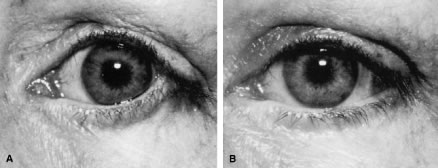

Ectropion and entropion share similar anatomic features. The most common predisposing anatomic factors for lower lid malpositions are horizontal eyelid laxity and weakness or defects of the lower lid retractors. The general weakness of the eyelid is caused by a weakness of the medial and lateral canthal tendons, permitting horizontal eyelid laxity.4 As such, it is best to consider lower eyelid laxity as resulting from laxity of the tarsoligamentous sling or support for the eyelid. The anatomic weakness can be demonstrated by the snap test. Downward retraction is exerted on the lower lid, pulling it away from the globe. On relapse, the lower lid should snap back against the globe spontaneously. Failure of the eyelid to snap back against the globe with a single blink indicates excessive laxity of the tarsoligamentous sling.

The development of ectropion and entropion is a reflection of the relationship between the anterior and the posterior lamellae. The eyelid position is maintained by an appropriate balance of the anterior and posterior lamellae. If tractional forces are unbalanced, eyelid malpositions may manifest as ectropion, entropion, or eyelid retraction. If traction is produced by the anterior lamella, either by chronic cicatricial changes or mechanical aberrations, the eyelid margin is everted away from the globe. This most commonly results from mild solar-induced changes or following surgical procedures or trauma of the eyelid, which produce a shortening or scarring of the skin and underlying orbicularis muscle.

Involutional entropion is more complex because of the multitude of factors producing this abnormality. The tarsal instability of entropic lids is due to horizontal eyelid laxity and loss of support of the lower eyelid retractors.10 The orbicularis muscle dynamics also assume a prominent pathophysiologic role in the production of entropion. In entropic eyelids, the preseptal orbicularis muscle overrides the pretarsal orbicularis muscle, which rolls the superior border of the tarsus internally. This is differentiated from spastic entropion, which is theoretically due to a spasm of Riolan's muscle. However, the primary differentiating feature of spastic entropion is a specific precipitating etiologic factor, such as recent eye surgery, eyelid edema, or ocular inflammation with secondary eyelid edema. An appreciation of the multiple etiologic causes of entropion has resulted in the evolution of combined approaches to correcting the various anatomic abnormalities and stabilizing the tarsus and orbicularis muscle.11–14